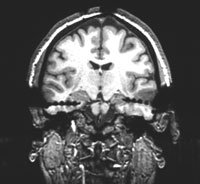

Pušenje utječe na rad mozga

Bolesti pluća koje su posljedica pušenja mogu dovesti do promjena u načinu funkcioniranja mozga, pokazuje istraživanje britanskih znanstvenika.

Čini se da se način funkcioniranja mozga mijenja kao odgovor na loše snabdijevanje kisikom. Znanstvenici iz londonskog Imperial Collegea su ispitivali rad mozga kod 8 pacijenata koji su bolovali od kronične upale pluća ili emfizema. Utvrđeno je da se mozak ispitanika postupno uspio prilagoditi manjku kisika i nastavio funkcionirati u otežanim uvjetima. Dobra je vijest da je mozak sposoban prebaciti se na normalno funkcioniranje kad se razina kisika u krvi povisi.